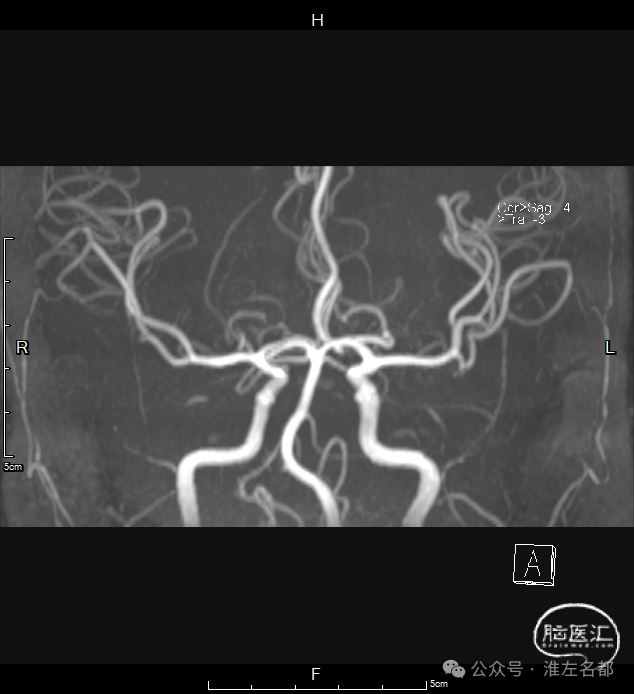

颅脑MRA:未及明确异常。